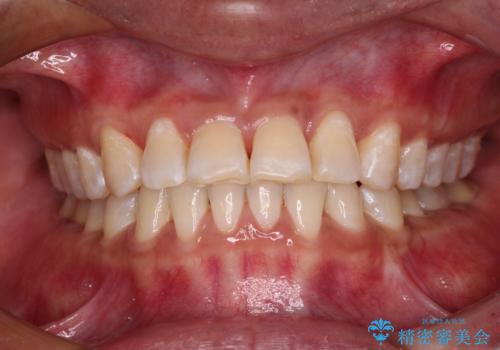

反対咬合の改善 途中で出産をしながらワイヤー矯正

- 治療期間

- 2年

咬合力が強く、反対咬合の改善に時間がかかりましたが、その後はスムーズに進めることができました。

途中、妊娠と出産があり、治療が中断したため、治療期間は延びましたが、出産も矯正治療も無事に終えることができました。